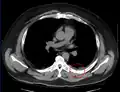

Fracture de côte sur un scanner thoracique Fracture de côte sur un scanner thoracique